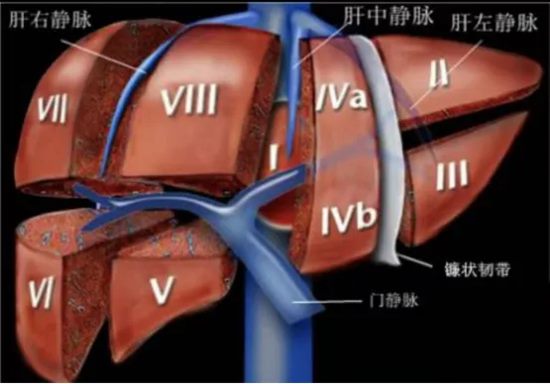

一、什么是右半肝切除?

右半肝切除,是指完整切除肝脏右半部分(含肿瘤),保留左半肝维持人体正常功能。

它主要用于:

1.肝右叶肝癌、肝血管瘤、肝内胆管结石

2. 肿瘤侵犯肝门、右肝静脉、门静脉右支等复杂情况

二、为什么说它难度极高?

右半肝切除被公认为肝脏外科金字塔尖的手术,难点在于:

1. 血管密布,如同“在血管上做手术”:右半肝紧邻门静脉、肝动脉、胆管、下腔静脉,稍有不慎就可能大出血。

2. 解剖复杂,操作空间极小:位置深、视野差,对医生的解剖熟练度要求极高。

3. 既要切得干净,又要保得住功能:切少了肿瘤易复发,切多了可能发生肝功能衰竭。

4. 腹腔镜下难度翻倍:微创视野有限,对精准分离、止血、缝合技术要求极高。

最终,手术历时约4小时,陈艳军主任团队冷静应对,精准解剖肝门Glisson系统,依次安全处理肝动脉、门静脉、肝静脉及肝短静脉,沿肝中静脉精准离断肝实质,在彻底切除肿瘤的同时,最大限度保留正常肝脏组织,实现了微创、精准、低出血、保功能的理想效果。